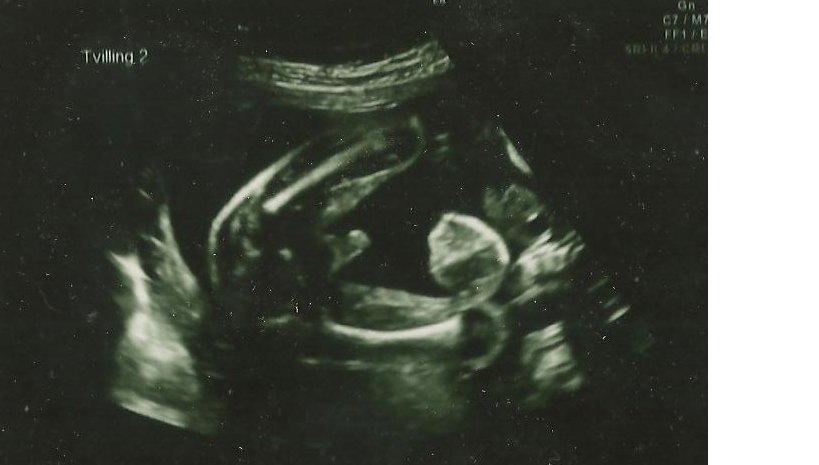

13+1 tvillinge b/Isabella